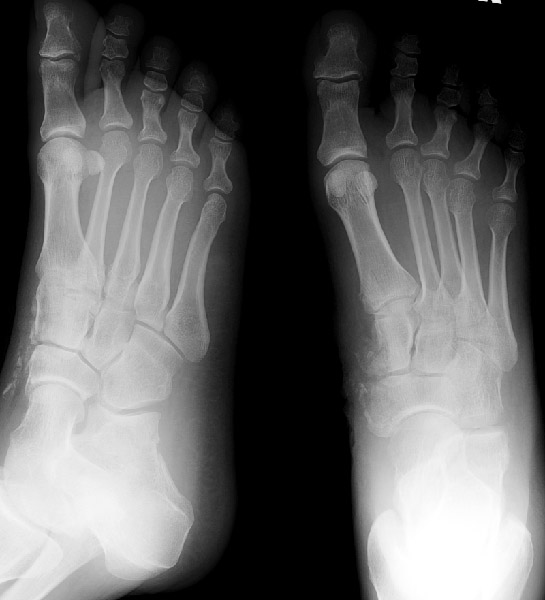

Return to Cuneiform Fracture